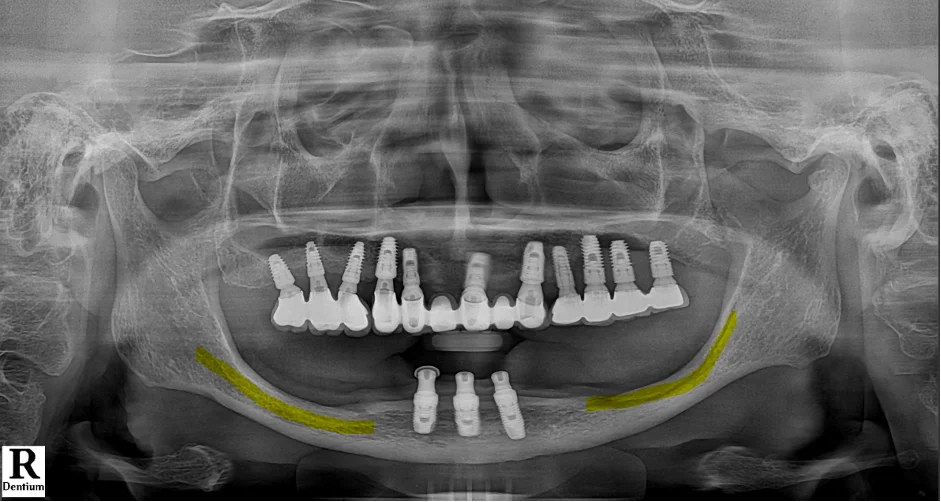

[📸 치료 전 엑스레이] (촬영일: 2024년 6월)

방사선 검사를 통해 전반적인 구강 상태를 확인해 보니,

아래턱 앞쪽에 기존 임플란트 3개가 식립되어

틀니를 지지하는 형태로 사용 중이셨으나

전반적인 씹는 기능이 크게 떨어져 있었습니다.

특히 아래턱 어금니 부위는 잇몸뼈 흡수가 심하고

신경선과 가깝게 맞닿아 있기 때문에,

다수의 임플란트를 심기 위한 뼈 높이 확보가

해부학적으로 매우 어려운 상태였습니다.